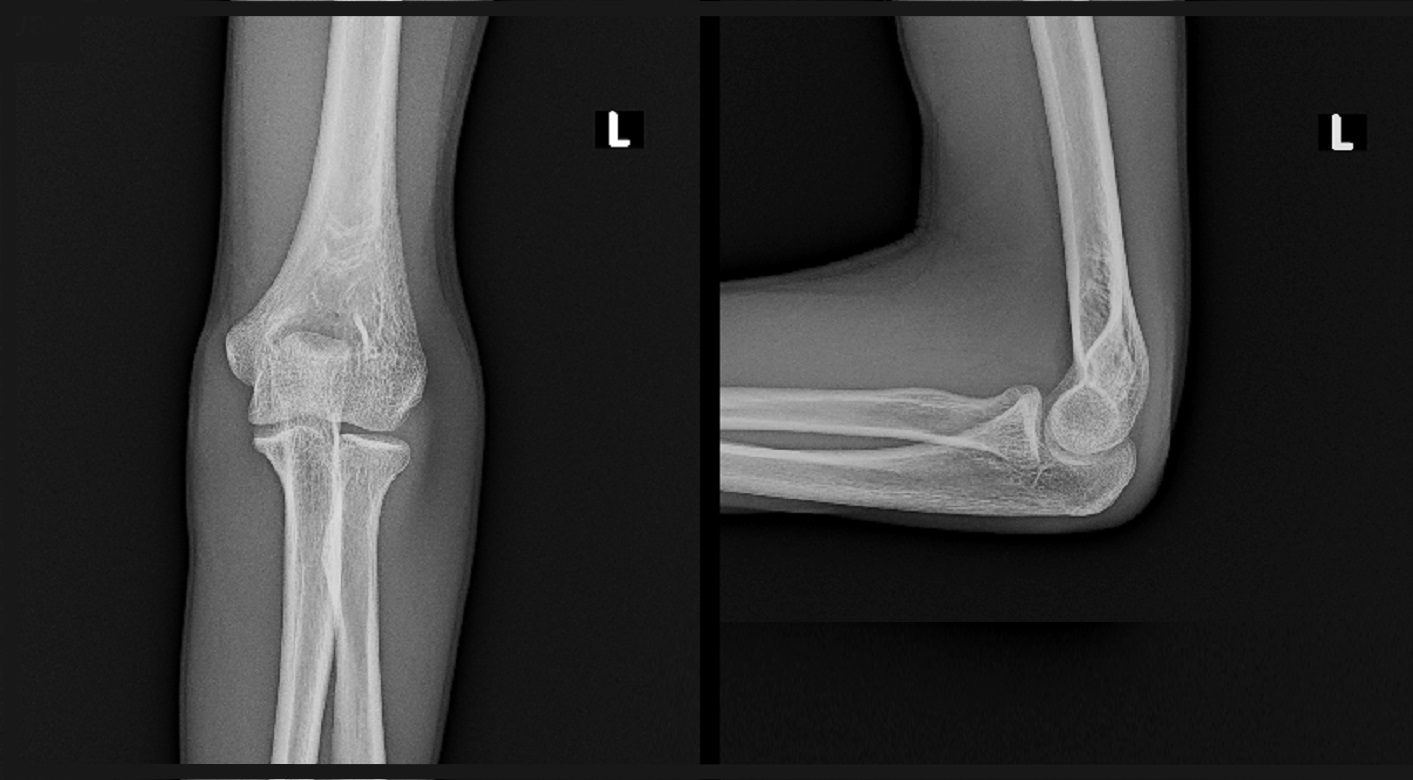

15才男 初診Xp.jpg

レントゲン像では異常はみられませんが、橈骨(親指側の骨)の関節側(赤丸部分)に圧痛を認めました。私はおそらく骨折があると思われるので、MRI検査で確認することを勧めました。